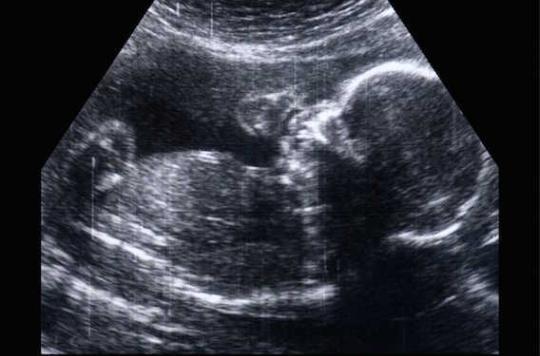

Si elles se révèlent justes (les autorités sanitaires ne souhaitent pas les commenter à ce jour), ces données fournissent une idée de l’ampleur que pourrait avoir le « scandale Dépakine ». Cet antiépileptique est responsable de malformations et de troubles neurocomportementaux chez les bébés exposés in utero.

Malgré ces effets secondaires connus, le Valproate de sodium a continué à être prescrit aux femmes enceintes. En février, l’Inspection générale des affaires sociales (Igas) a évalué à 450 le nombre d’enfants nés avec des malformations congénitales entre 2006 et 2014 après avoir été exposés au valproate pendant la grossesse de leur mère.